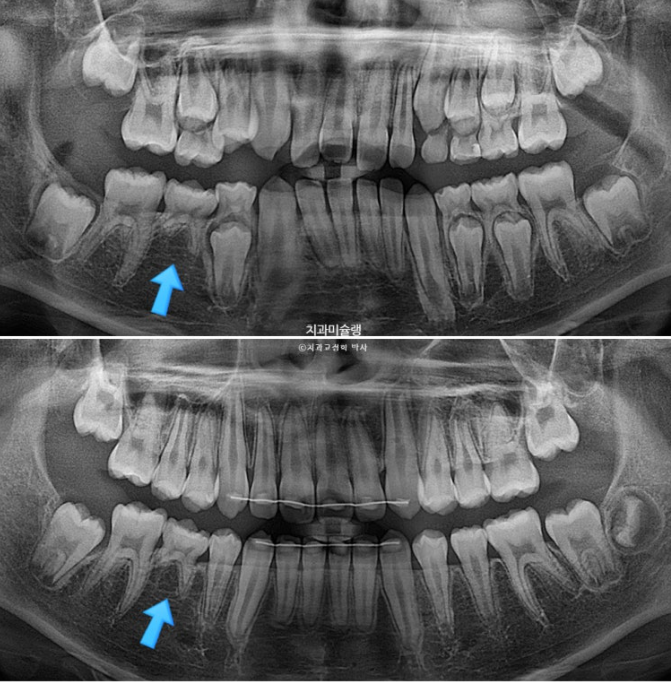

파란화살표 자리에 있어야할 작은어금니가 선천적 결손 상태입니다.

이런 경우 계승영구치가 없어 오래도록 남아있게될 잔존유치를 최대한 보존해서 쓰는 방법으로 치료를 합니다.

잔존유치를 오래 보존해서 사용하기로 했다면 교정 치료 중 불필요한 치아이동에 의해 잔존유치치근이 녹아 짧아지지 않도록 각별히 신경써야 합니다.

유치는 교정력을 받았을때 영구치와 다르게 잘 움직이지 않을 뿐더러, 안그래도 영구치에 비해 뿌리가 약한 상태이니 치근흡수라도 나타나면 발치해야 하는 애매한 상황이 생깁니다.

파란 화살표 잔존유치는 초진에 비하여 치근흡수 없이 잘 보존되었습니다.

다른 영구치들에 치근흡수는 없고 치근평행도는 좋습니다.

선천적 결손이라고 해도 치료를 잘 해주면 별 문제 없이 교정 마무리가 가능합니다.